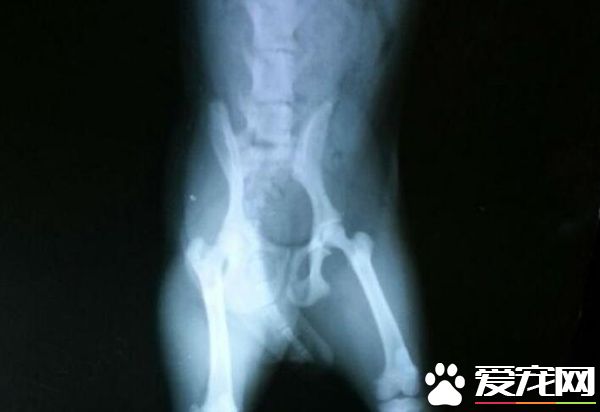

髋关节发育不全,第一是遗传因素,大多这种情况是狗狗出生就有的现象,极少为突发性的;第二是从小营养不良问题而影响的骨骼发育,变现出的症状与关节炎相似,可以去宠物医院进行X光诊断出。另外可查看狗狗是否有骨折、关节错位等症状。需要根据医生的诊断和建议,考虑是否进行手术。如果情况较轻,可以服用“汪想关节宝”等药物来进行保守治疗。 患关节炎大多发生在年老狗狗以及体型过胖的狗身上,另外如果狗狗经常卧睡于凉地板上、运动量过于太大所致的关节磨损、以及长期身处于阴凉潮湿环境之中,都是较容易患关节炎的因素。在泰迪腿瘸的时候,一定要意识注意到问题的严重性,以免错过治疗的最佳时机。 第三种:钙的缺乏